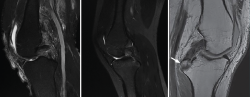

The anatomical references for arthroscopically recognizing the tibial insertion site of the PCL are the most posterior and lateral fibers of the posterior horn of the medial meniscus (Figure 10), defined as shining white fibers that delimit the insertion site medially, and the fibers of the popliteus muscle that indicate the distal margin (27).

Figure 10. A: view from a transpatellar (Gillquist) portal. From the posteromedial working portal we use radiofrequency to clean the tibial insertion site of the posterior cruciate ligament (PCL) which is located in the posterolateral zone of the posterior root of the medial meniscus (arrow); B: view from a posteromedial portal. Fully cleaned tibial insertion site with the arrow indicating the posterior root of the medial meniscus.